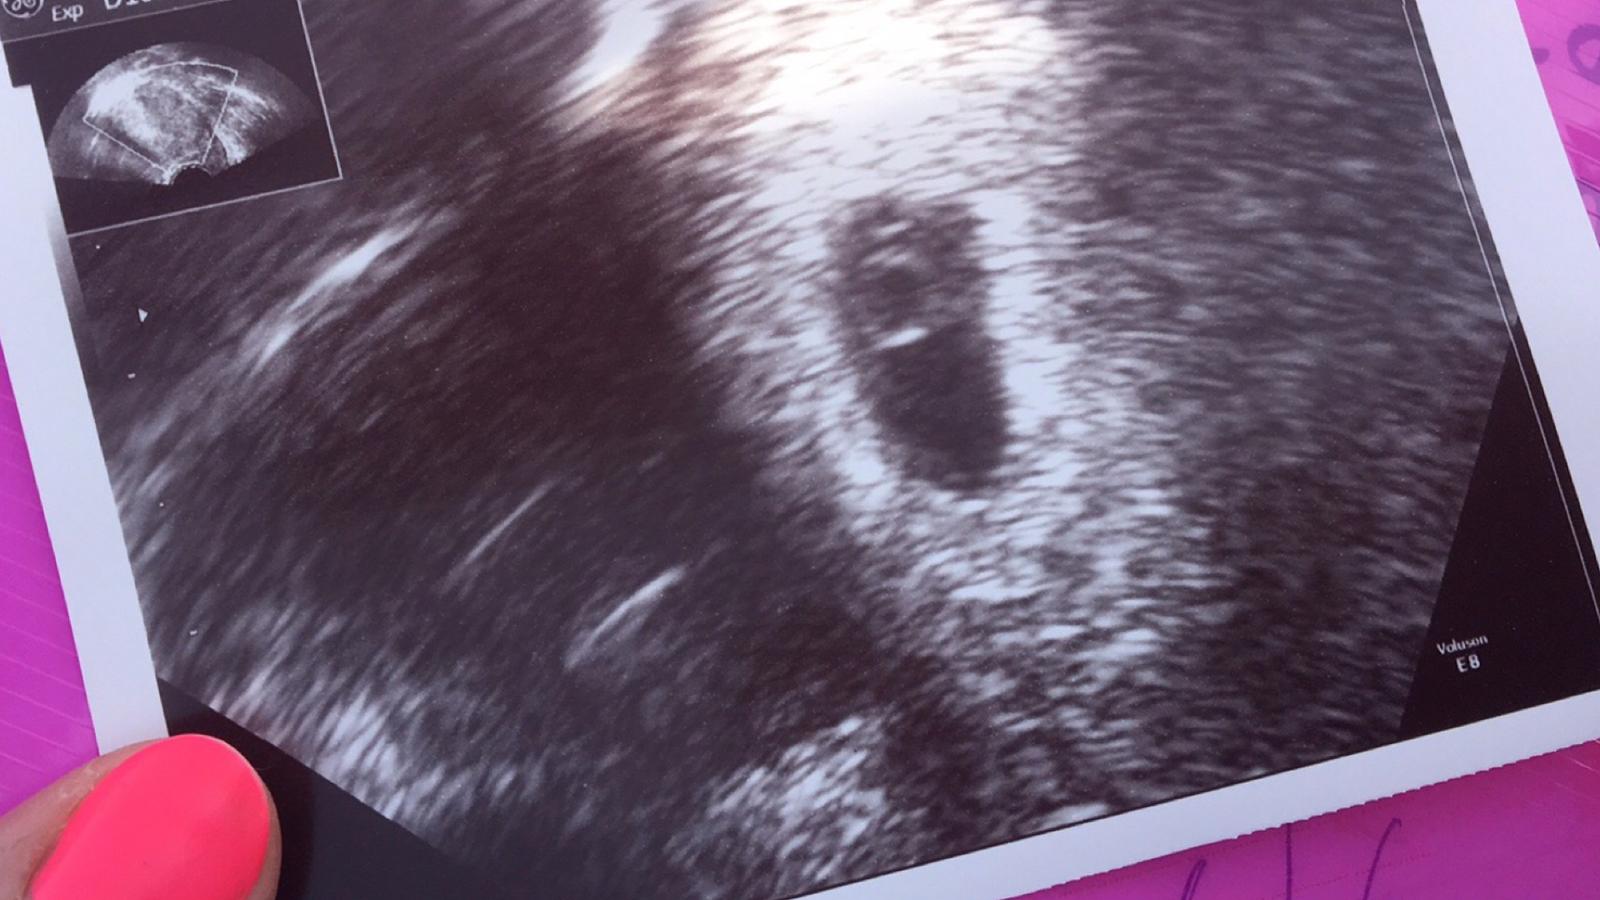

Ahoj holky. Mam po kontrole. Tomu neuverite. Gynekolozka mi minuly tyden vyfotila dve dutiny a rekla, ze to jsou dvojcata. Nicmene dnes mi jina dr rekla, ze mi vyfotila pouze me cysty na vajecniku. A miminko nasla tam, kde ma byt 😍 Nechapu, jak se to muze stat. Nejdriv jsem prozivala sok, ze cekame dvojcatka a ted sok, ze to neni pravda. Jinak tehotenstvi mi dle uz odpovida 5+6 (podle ovulace) misto 6+2 (podle ms). Nicmene jsem strasne stastna 😍

@llenka_li jeste ne. Pry v tom sestem tydnu to jeste byt nemusi a navic ja byla z toho vseho tak nervozni, ze jsme videli, jak mi tepe brisni aorta a trepalo to i s plodem. Na dalsi sono jdu za 3 tydny 🙏